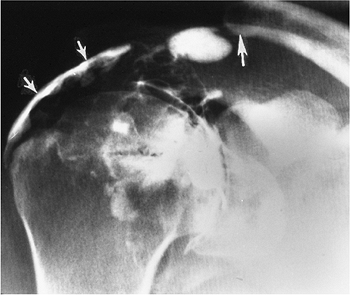

FIGURE 7-4 Anterior dislocations. (A) AP radiograph shows an anterior dislocation with fracture fragments laterally. (B) AP postreduction radiograph shows the tuberosity fracture (arrow) and Bankart lesion (open arrow) adjacent to the inferior glenoid. (C) AP radiograph demonstrates an impaction fracture (arrows) or Hill-Sachs lesion in a patient with a prior dislocation.